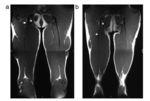

Cada una de las imágenes RM fue valorada por uno de los dos radiólogos osteomusculares, que fueron cegados al resultado clínico. Cada radiólogo calificó las RM en un orden aleatorio, entre julio de 2009 y julio de 2016. La medición del tendón libre proximal del CLBF se muestra en las figuras 1 y 2.

Figura 1. La longitud del tendón libre proximal del CLBF se mide (en cm) desde el margen más inferior de la tuberosidad isquiática hasta el punto en que las primeras fibras musculares comienzan a insertarse en el tendón. a) Tendón libre corto. b) Tendón libre mediano. c) Tendón libre largo.

CLBF: cabeza larga del bíceps femoral; ST semitendinoso; TI: tuberosidad isquiática; *: tendón libre.

Figura 2. Se muestran imágenes de RM coronal T1 de un tendón libre corto (a) y un tendón libre largo (b). Las puntas de flecha muestran el margen más inferior de la tuberosidad isquiática y las flechas muestran el punto en que las primeras fibras musculares comienzan a insertarse en el tendón.